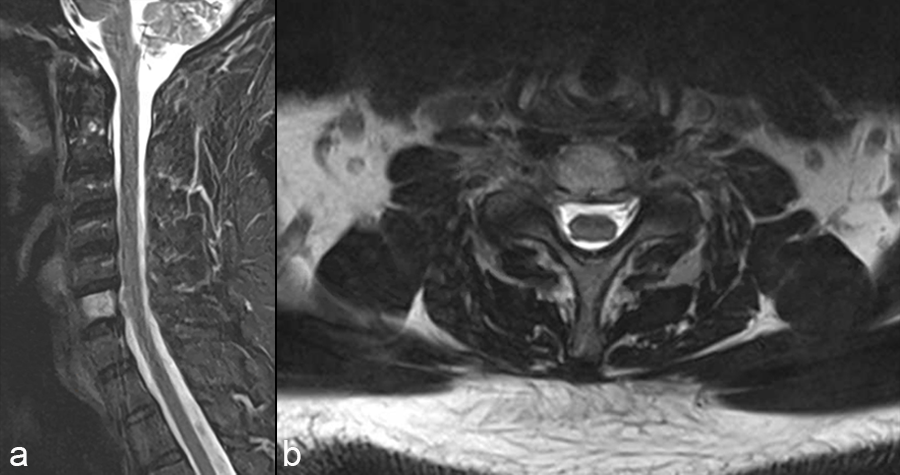

A 47-year-old male presented with neck pain. Upon examination, he was neurologically intact. He underwent an MRI of the cervical spine that demonstrated a non-enhancing T1-hypointense and T2-hyperintense lesion (Fig 1).

The patient underwent a CT guided biopsy that demonstrated a brachyury positive lesion consistent with a chordoma versus benign notochordal tumor. He underwent a two-stage operation for en bloc resection of the lesion. Cervical spine stabilization was achieved using CMORE® Carbon/PEEK implants. The radiolucent nature of these implants permits artifact-free postoperative imaging and more precise radiation treatment, an important consideration in patients with spinal tumors.

The anterior cervical spine was reconstructed from C5-C7 using tricortical iliac crest autograft and an icotec Carbon/PEEK anterior cervical plate system (Fig 4). Following reconstruction, imaging (Fig 5) demonstrated no MRI artifact in the sagittal (a,c) and axial (b,d) planes.